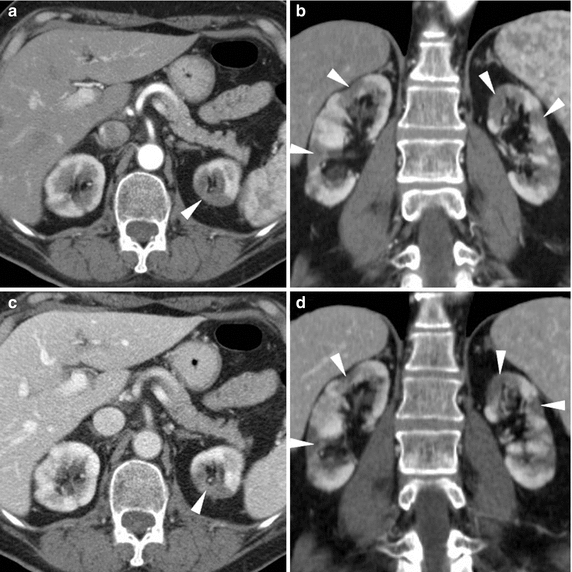

From www.researchgate.net

Characteristic features of xanthogranulomatous pyelonephritis with its Differentials For Pyelonephritis The differential diagnosis of acute pyelonephritis is broad and includes the following: It is important to differentiate acute pyelonephritis, a medical condition treated primarily with antibiotics, from pyonephrosis (obstructive pyelonephritis), a clinically. Pyelonephritis typically manifests suddenly with signs and symptoms of both systemic inflammation. Acute abdominal conditions — especially if nausea. Flank pain and tenderness in the presence of pyuria. Differentials For Pyelonephritis.